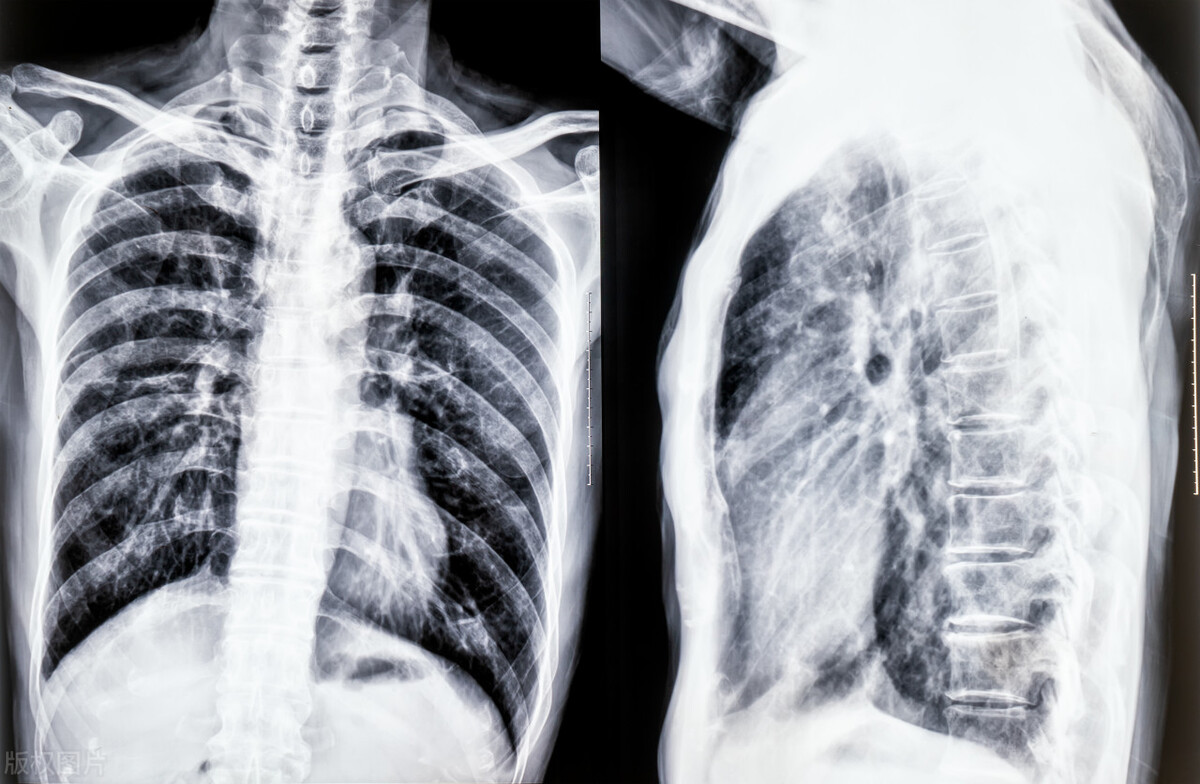

3、胸部X光:当患者出现胸痛时,胸部X光检查可以为医生提供有价值的信息。它有助于确定胸痛的原因,如肺部塌陷、心脏病发作或其他医疗状况。它还可以帮助排除其他可能导致胸痛的原因,例如肌肉拉伤或肋骨拉伤。

胸部X光检查是一种安全、无创的检查方法。患者将被要求躺在桌子上,X光机将放在他们上方。患者在手术过程中需要保持静止,通常需要不到10分钟。